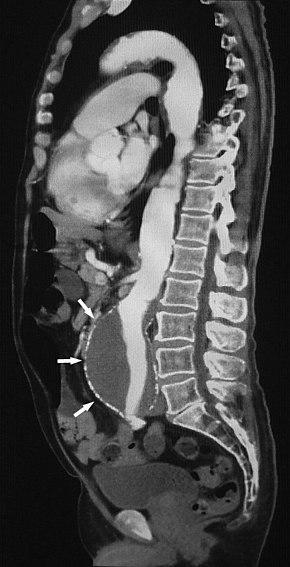

SagitalAAA.jpg

Sagittal thin slice of a computed tomography angiography abdominal aortic aneurysm (AAA) (arrows)

Aorta and great arteries

CTA can be used in the chest and abdomen to identify aneurysms in the aorta or other major blood vessels. These areas of weakened blood vessel walls that bulge out can life-threatening if they rupture. CTA is the test of choice when assessing aneurysm before and after endovascular stenting due to the ability to detect calcium within the wall.[2] Another positive of CTA in abdominal aortic aneurysm assessment is it allows for better estimation of blood vessel dilation and can better detect blood clots as compared to standard angiography.[3]

CTA is used also to identify arterial dissection, including aortic dissection in the aorta or its major branches. Arterial dissection is when the layers of the artery wall peel away from each other; this causes pain and can be life-threatening. CTA is a quick and non-invasive method of identifying dissections and can show the extent of the disease and if there is leakage.[3]